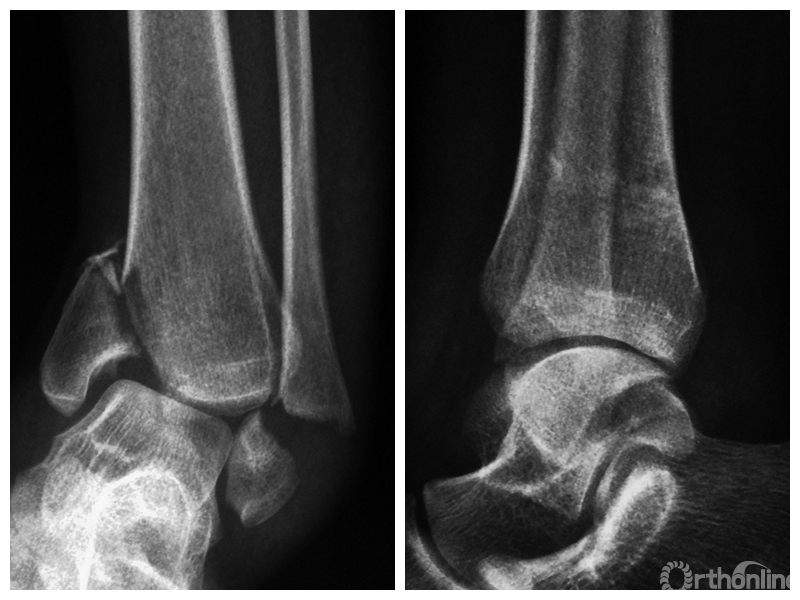

两组患者均获随访,支撑钢板固定组随访时间46~91,平均64.5个月;螺钉固定组随访时间44~86,平均59.5个月。支撑钢板固定组患者术后完全负重时间为(11.5±1.6)周,较螺钉固定组的(12.6±2.3)周显著缩短,比较差异有统计学意义(t=2.05,P=0.04)。X线片复查示,支撑钢板组均获解剖复位,均达愈合;螺钉固定组有20例获解剖复位,2例畸形愈合,1例不愈合,支撑钢板组骨折愈合时间为(11.5±1.6)周,螺钉固定组为(12.0±1.7)周,比较差异无统计学意义(t=1.06,P=0.30)。见图1、2。支撑钢板固定组3例(10%)、螺钉固定组4例(17.4%)发生创伤性关节炎,均采取保守治疗;两组比较差异无统计学意义(P=0.45)。

图1 支撑钢板固定组患者,女,63岁,右侧旋后-内收型II度踝关节骨折 a. 术前正侧位X线片;b. 术前CT;c. 术后2周正侧位X线片;d. 术后2年正侧位X线片

图1d 术后2年正侧位X线片

图2 螺钉固定组患者,女,37岁,左侧旋后-内收型II度踝关节骨折 a. 术前正侧位X线片;b. 术前CT;c. 术后2周正侧位X线片;d. 术后1年正侧位X线片

图2d 术后1年正侧位X线片